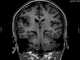

Perisylvian syndrome is a rare neurological disease characterized by damage to the sylvian fissure (lateral sulcus), an area in the brain involved in language and speech. The main symptoms are difficulty chewing and swallowing, low muscle tone in the face and tongue, speech and language development disorders, and epilepsy. [Source: Wikipedia ]